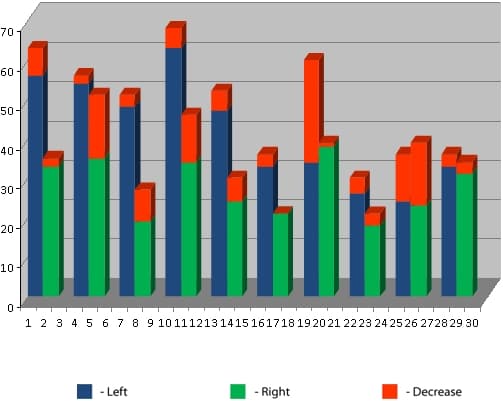

Assessment of the effect of the Aires Defender using Nakatani functional diagnostics.

Another test group was evaluated using Nakatani functional diagnostics. Observations were performed using a Mediscreen rapid-diagnostic apparatus.

The results are presented as diagnostic charts and circular charts.

The diagnostic charts are interpreted as follows: The middle band is the range of normal values (green meridians). From the right is the activation band (red meridians). From the left is the depressed activity band (red meridians).

The circular charts are interpreted as follows: The blue line is the left side. The green line is the right side. The red dashed line is the generalized measurement. The normal band is green.

We offer some examples below.

1. 68-year-old female test subject.

Diagnostic charts before application of the Aires Defender (Fig. 1) and after application for three days (Fig. 2).

These diagnostic charts show that initially energy resources are low – the average value is 28, with a norm from 25 to 55. Metabolic processes were retarded and there were signs of intoxication (Yin/Yang 1.36, with a norm of 0.9-1.1). There was a pronounced psychological and emotional load (top/bottom 1.44, with a norm of 0.8-1.2). Metabolic processes in the tissues of the locomotive mechanism were disrupted (left/right 0.88, with a norm of 0.9-1.2).

The charts is asymmetric due to the depression of some meridians and the activation of others, which indicates an imbalance of the oscillatory (wave) processes in the body. The test subject is in a high-risk group for developing serious diseases.

Under the influence of the Aires Defender, the level of functional activity was raised significantly, energy resources grew from 28 to 40, intoxication decreased, and the psychological and emotional state normalized.

The potential of most of the meridians were established in the range of normal values.

Test subject’s circular charts before the Aires Defender (Fig. 3) and after the Aires Defender (Fig. 4):

The blue line is the left side. The green line is the right side. The red dashed line is the generalized measurement.

Before using the Aires Defender, a pronounced asymmetry of the circular charts was observed due to the depression of some meridians and the activation of others.

After the effect, the chart’s asymmetry was substantially reduced and the majority of the measures were in the normal range (green band).

2. 46-year-old female test subject.

The test subject’s diagnostic chart at the beginning of the workday before the use of the Aires Defender (Fig. 1) and after 6 hours of working at a computer monitor with the Aires Defender (Fig. 2).

Before using the Aires Defender, the average energy resources were 32, with a norm from 25 to 55. The removal of metabolic toxins was retarded (Yin/Yang 1.31, with a norm of 0.9-1.1). Metabolic processes in the tissues of the locomotive mechanism were disrupted (Left/Right 0.74, with a norm of 0.9-1.2). The endocrine system was in a dysfunctional state.

At the end of a working day under the protection of an Aires Defender, energy resources did not fall, but rather increased from 32 to 39. Measurements for most of the meridians normalized, indicating an increase in the functional level despite the subject working for 6 hours at a computer monitor.

The test subject’s circular charts at the beginning of the workday (before application of the Aires Defender) (Fig. 3) and after working for 6 hours with the Aires Defender (Fig. 4).

Before applying the Aires Defender, a moderate asymmetry of the charts was observed due to the depression of some meridians and the activation of other meridians.

After 6 hours of working under the protection of the Aires Defender, the circular chart became more symmetric and measurements for the majority of the meridians were in the normal range of values (green band).

These tests using Nakatani functional diagnostics confirm that the Aires Defender is highly effective as a means of universal protection of the body against man-made electromagnetic radiation.

Especially obvious are the results of the 46-year-old test subject who, after working for 6 hours at a computer monitor, experienced an increased functional level accompanied by an increased capacity to work, the absence of fatigue, and the preservation of feelings of well-being at the end of the workday.